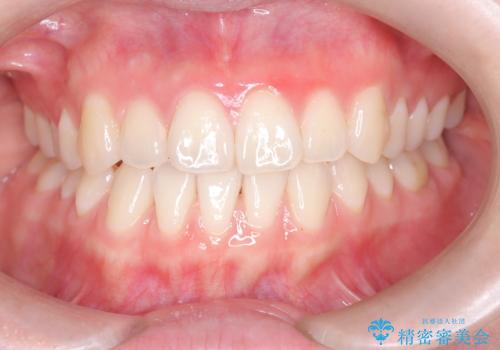

八重歯と前歯の逆の咬み合わせを、目立たない矯正で同時に改善

今回の矯正治療では、透明なマウスピース型の装置インビザラインを使用しました。治療は、緻密なデジタル計画に基づき、奥歯から順に歯列全体を後方へ移動させる遠心移動を実施。これにより、八重歯を正しい位置に並べるためのスペースを確保しました。同時に、右上の2番を前方に誘導することで反対咬合を解消。結果として、抜歯することなく八重歯と反対咬合という複数の問題が改善され、機能的で美しい歯並びを獲得していただけました。